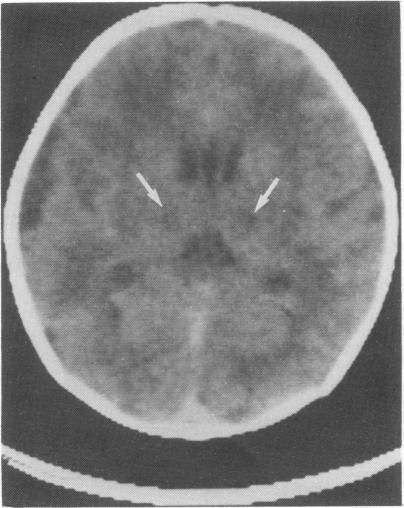

Clinical observations and findings on imaging are reported in six newborns with symmetrical thalamic lesions (STL). In three cases the diagnosis was confirmed by postmortem examination. Characteristic observations in this series and 17 previously reported cases include no evidence of perinatal asphyxia, high incidence of polyhydramnios, absent suck and swallow, absent primitive reflexes, appreciable spasticity at or within days of birth, lack of psychomotor development, and death within days or months. Characteristic pathological findings include loss of neurons, astrogliosis, and 'incrusted' neurons particularly in the thalamus. In two thirds of cases the basal ganglia and brain stem are involved as well. A hypoxic-ischaemic event occurring two to four weeks before birth is most likely responsible for STL. Bilateral thalamic calcification can often, but not always, be demonstrated in the newborn period by computed tomography and/or cranial ultrasound. The presence of these calcifications and the observation of spasticity at birth imply that the responsible insult occurred at least two to four weeks earlier. The small number of published cases with STL suggest that it may be easily missed.